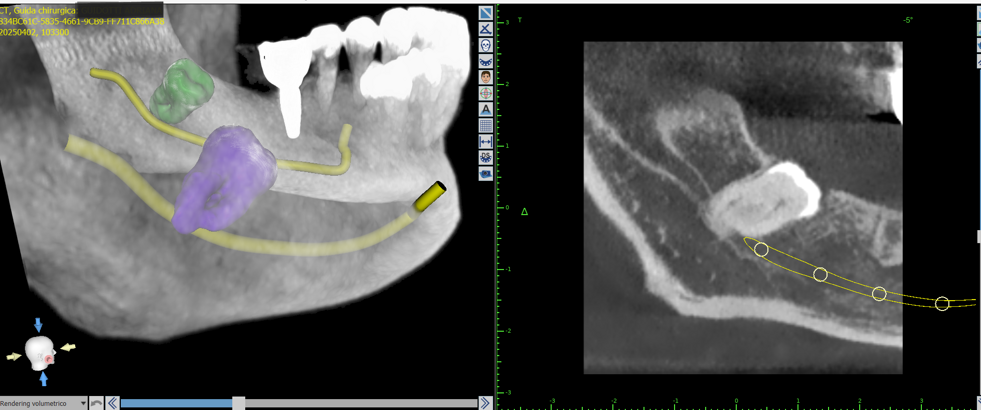

La chirurgia orale supportata da software 3D rappresenta un'evoluzione fondamentale nel trattamento dei denti del giudizio inclusi. La capacità di visualizzare e pianificare l'intervento in un ambiente virtuale offre un livello di precisione e sicurezza senza precedenti, traducendosi in benefici concreti per il paziente in termini di riduzione del disagio e di un recupero più rapido. Sebbene richieda un investimento in tecnologia e formazione, questo approccio si sta sempre più affermando come la scelta d'elezione per i casi più complessi e per garantire i più alti standard di cura.

Il processo inizia con una tomografia computerizzata (CBCT), che fornisce un’immagine tridimensionale dettagliata delle arcate dentarie e delle strutture ossee. I dati vengono importati in software dedicati, dove il chirurgo può pianificare virtualmente l’intervento: scegliere la posizione, l’inclinazione e la profondità ottimali di ciascun impianto, valutando anche la densità ossea e la distanza da nervi o seni mascellari.